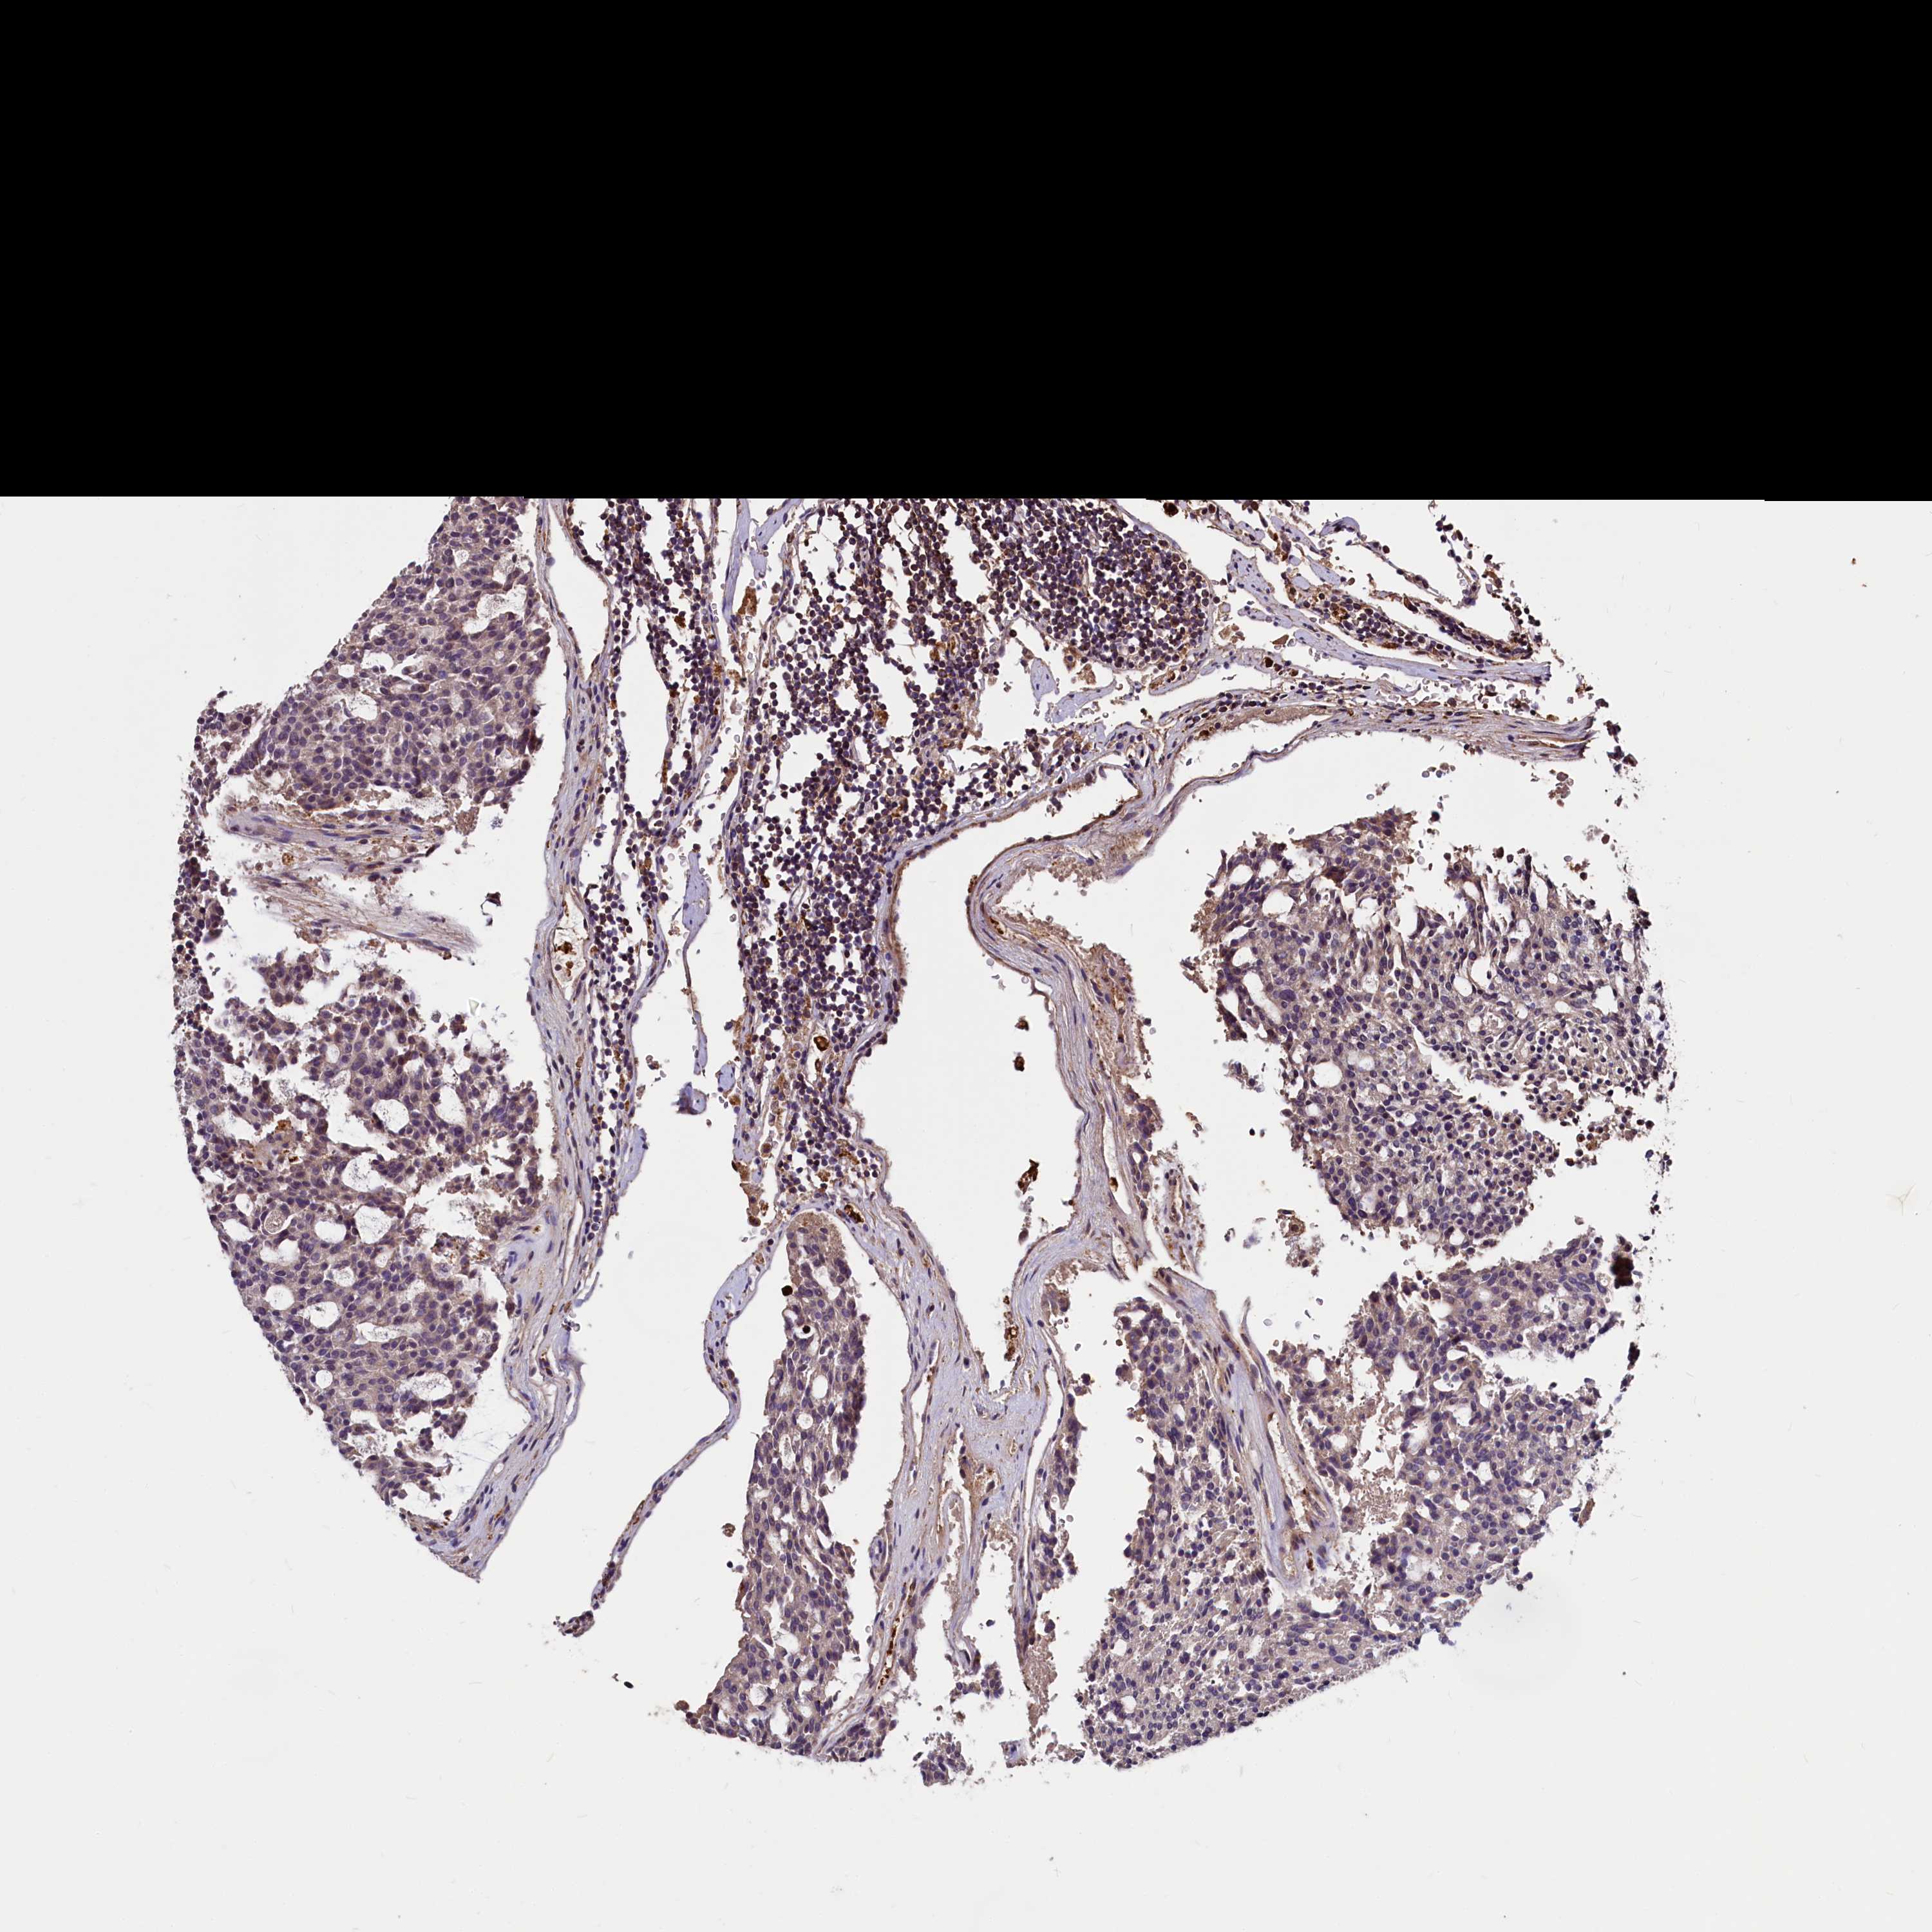

CARCINOID - Protein expressioni

A mouse-over function shows sample information and annotation data. Click on an image to view it in a full screen mode. Samples can be filtered based on level of antibody staining by selecting one or several of the following categories: high, medium, low and not detected. The assay and annotation is described here.

Each image is clickable and will lead to virtual microscopy that enables deeper exploration of all samples and also displays staining intensity scores, fraction scores and subcellular localization as well as patient and tissue information for each sample.

Antibody HPA039904

Staining

High

Medium

Low

Not detected

Intensity

Strong

Moderate

Weak

Negative

Quantity

>75%

75%-25%

<25%

None

Location

Nuclear

Cytoplasmic/membranous

Cytoplasmic/membranous,nuclear

Carcinoid, malignant, NOS

Carcinoma, NOS